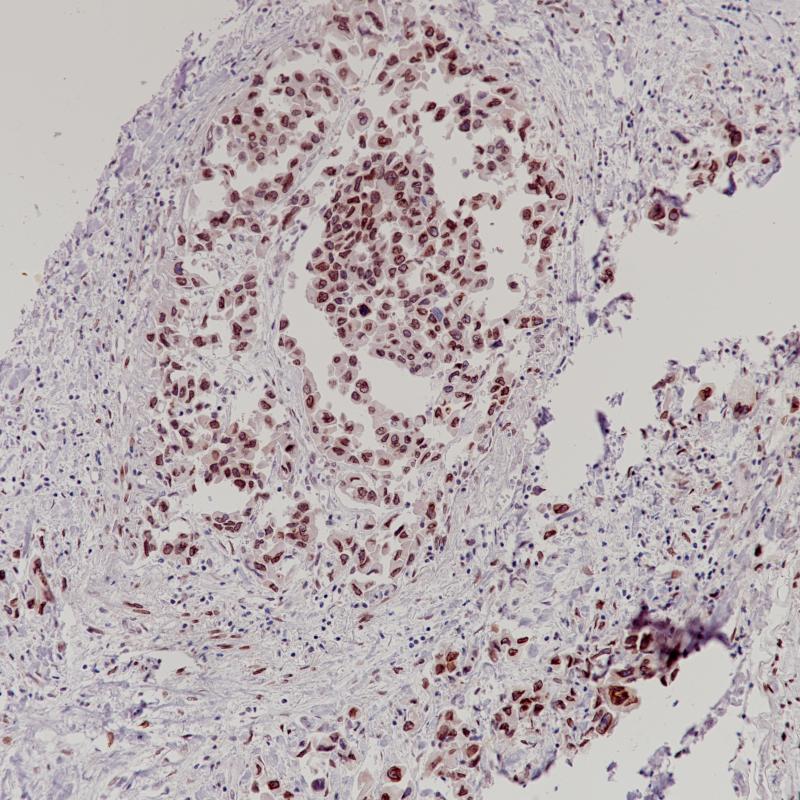

肺腺癌CDK4(BP6230)染色

细胞周期蛋白依赖性激酶4 (CDK4)是一种参与细胞周期的蛋白丝氨酸激酶。CDK4在高分化和去分化脂肪肉瘤中高表达,但在其他良性脂肪肉瘤和其他肉瘤中很少表达。CDK4联合MDM2可鉴别高分化脂肪肉瘤(+)、去分化脂肪肉瘤(+)和黏液样脂肪肉瘤、多形性脂肪肉瘤、梭形脂肪瘤等高级别肉瘤。

亚细胞定位

细胞核